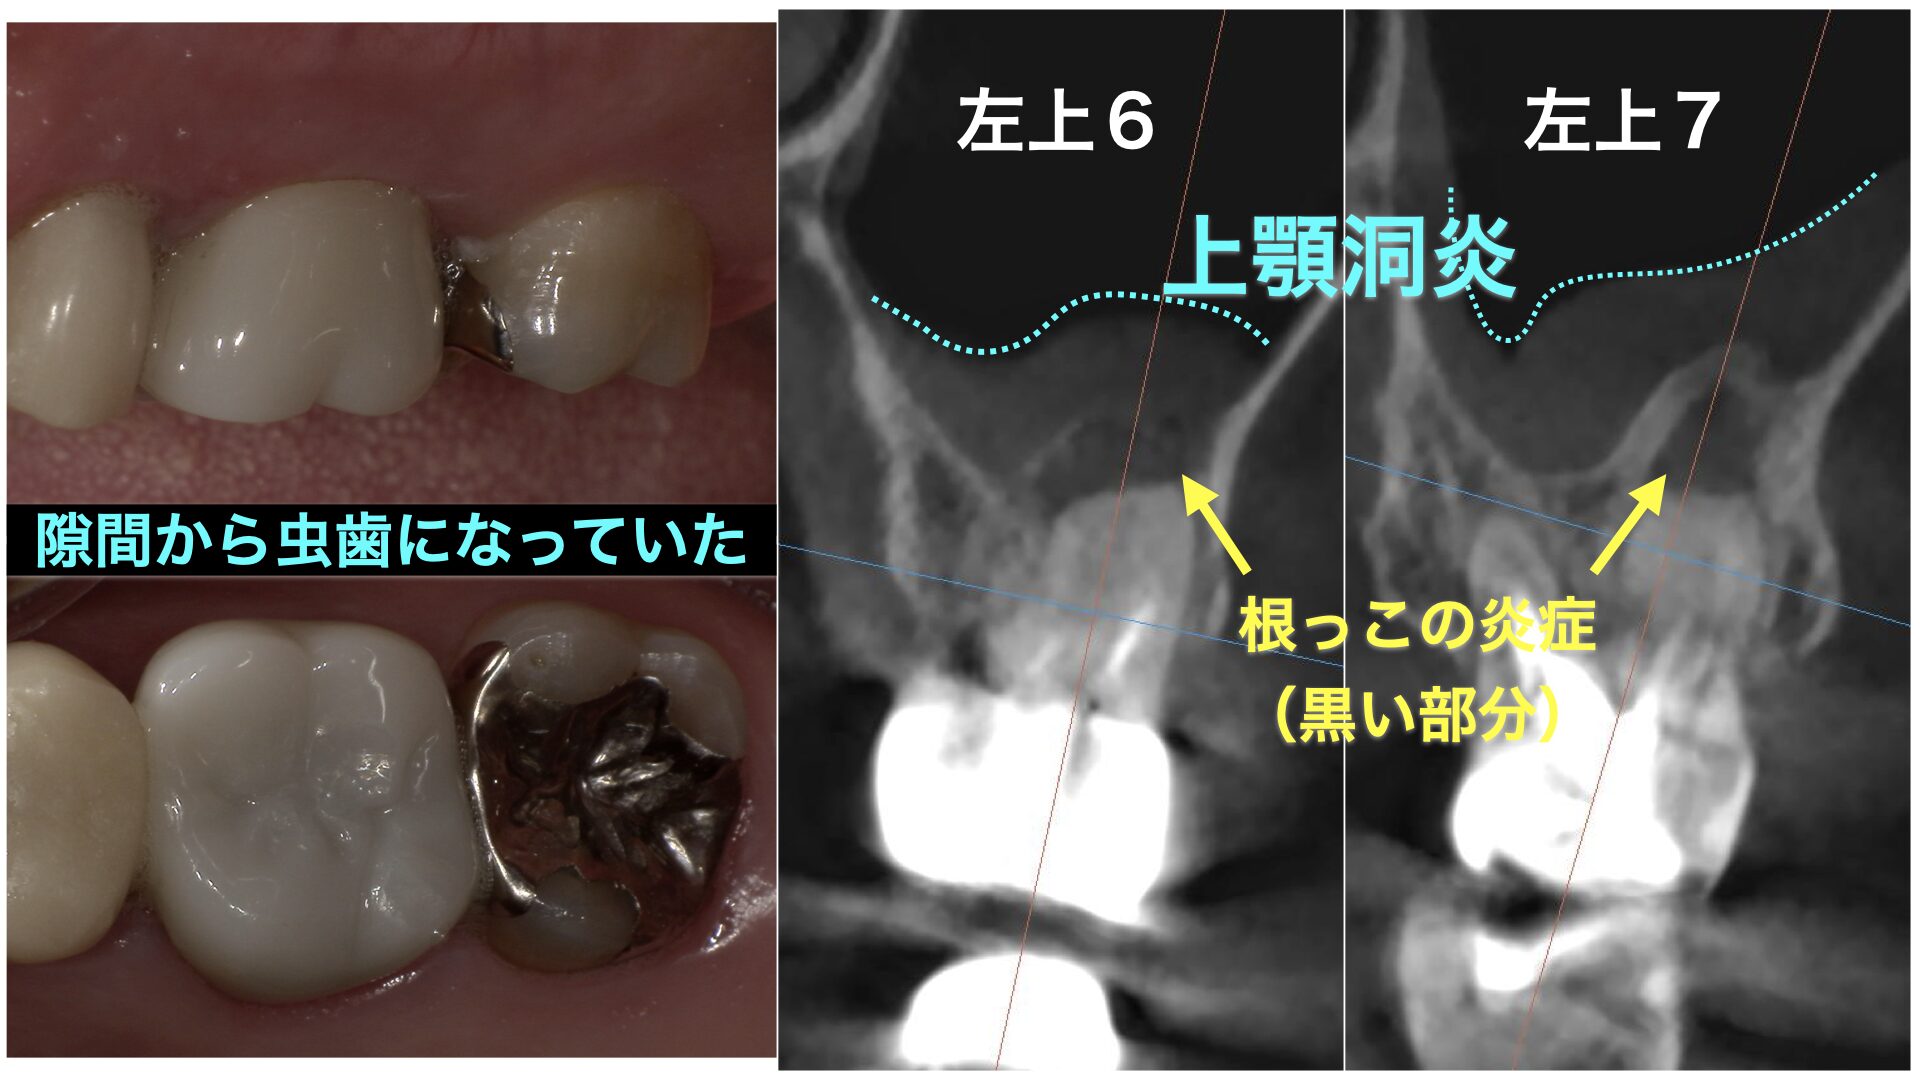

CASE 症例紹介

当院では、歯周病治療やインプラント治療、セラミック治療、審美治療など、様々な治療オプションを用いて、お口の中全体を管理しています。

院長が施術してきた症例をご確認のうえ、お気軽にご相談・ご来院ください。